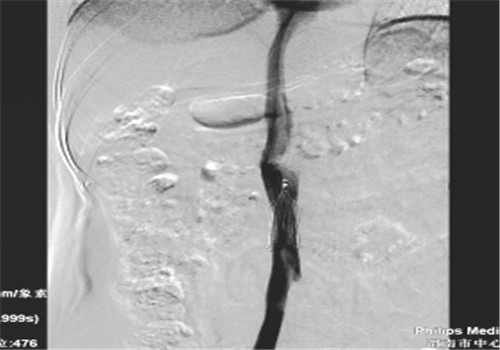

患者中年男性,一年前外伤多处骨折合并右下肢深静脉血栓形成,为确保骨科术中术后安全、有效避免肺栓塞发生,骨科术前介入行下腔静脉可回收滤器置入术。术后规范抗凝一月后复查无下肢深静脉血栓。

8月中旬患者来院复查,顺利骨取出科钢板,右下肢未见深静脉血栓,于8月14日行下腔静脉滤器取出术,手术顺利,历时30分钟。